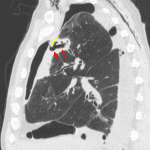

Age: 47

Sex: Male

Indication: Empyema

Sample ReportModerate-sized multiloculated right hydropneumothorax with apically-directed right thoracostomy tube in place, consistent with the clinical suspicion for empyema.

Focal area of consolidation and cavitation in the anterior aspect of the right upper lobe with an associated bronchopleural fistula. This area of consolidation could represent an abscess or cavitary neoplasm.

Extensive right chest wall subcutaneous emphysema.